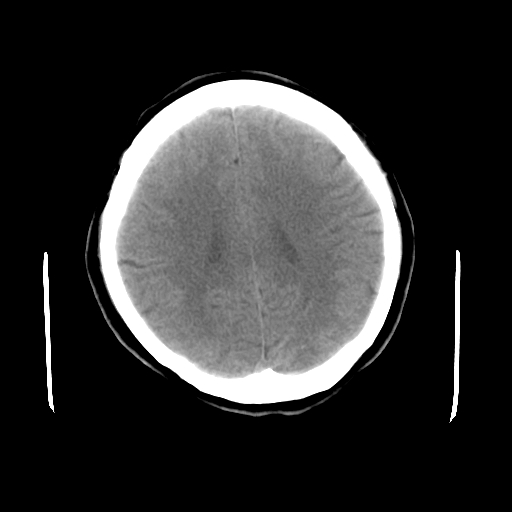

标题: CT23995:女,42岁,前额部外伤1小时,伤后头痛。 [打印本页]

女,42岁,前额部外伤1小时,伤后头痛。

头颅ct平扫未见异常

未见明显异常!

颅脑ct平扫未见异常,必要时复查

未见明显外伤性改变。

未见明显异常